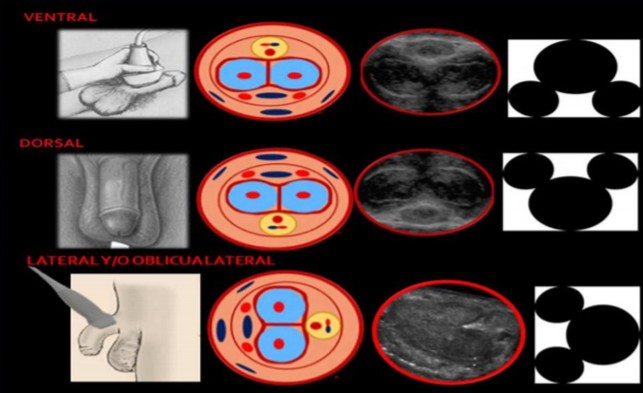

Con el fin de evaluar la integridad anatómica del pene y su funcionamiento es que recomiendo siempre realizar un estudio doppler (duplex). Este estudio de urltrasonografía va a mostrarnos la calidad de los componentes del pene: cuerpos cavernosos, esponjosos, uretra y túnicas que lo recubren; pero además, nos va a decir cómo los vasos sanguíneos funcionan, y si funcionan bien.

Realizar un Duplex peniano implica hacer una ecografía antes y después de aplicar una sustancia vasoactiva en el cuerpo cavernoso del pene, como vemos en la figura de arriba. La intención es ver cómo se comportan los vasos sanguíneos en el estado de flacidez y de erección, al suponer que el sujeto no tiene ninguna alteración, lo lógico es esperar que el flujo de sangre aumente al aplicar la sustancia; si esto no sucede posiblemente estemos ante una falla vascular, y estemos descubriendo la causa de la disfunción eréctil.

El punto óptimo de exploración con el transductor es en la base del pene, justo después de la bifurcación caverno-dorsal donde el ángulo de exploración es más adecuado

Debemos realizar la exploración ecográfica de cuatro puntos importantes: